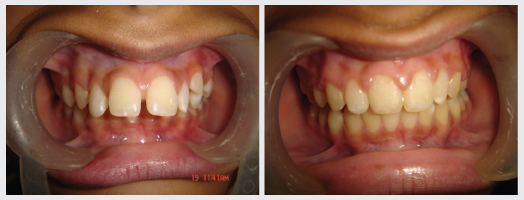

Orthodontics, popularly known as Braces treatment is a speciality of Dentistry that deals with the correction of Malocclusion or Malalignment. It is used to correct crowded teeth, protruded teeth, dental spaces, Jaw Deformities, improper bites and crooked smiles. At DENTAL QUE Orthodontic treatment is done for all age groups and there are types of braces available to suit everyones needs.